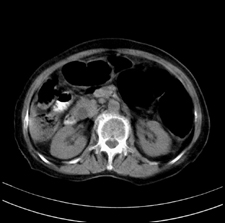

患者,女,75岁。腹痛,体黄5日,膝胸位时腹痛缓解。肝功能明日出来。彩超提示胆总管占位,未见血流信号。心电图提示s-t段改变。患者体质较弱,未能增强。

胆总管结石

胆总管多发结石

胆总管多发结石伴肝内外胆管轻度扩张。

胆总管上段,腔内有软组织密度影 ,ct值36-44hu。大家看有没有胆管癌的可能。

典型胆总管多发结石;增强扫描前后ct值是否发生改变是鉴别结石与占位的依据。